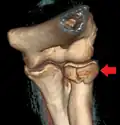

CT scan showing a radial head fracture -

Radial head fracture seen on 3D CT reconstruction